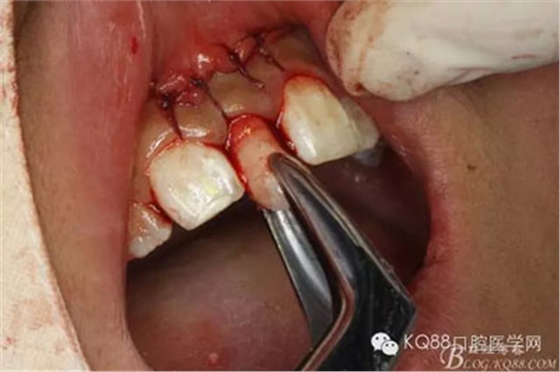

圖5.金屬吸唾管隨時(shí)吸凈血液,保持術(shù)野清晰

圖6.翻瓣、暴露唇側(cè)骨質(zhì)

圖7.小骨鑿去除骨質(zhì)

圖8.適當(dāng)采用高速手機(jī)精細(xì)去骨